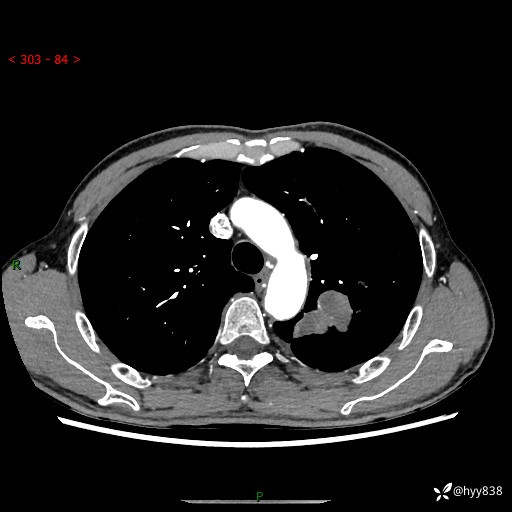

现病史:患者余4月前发现咳嗽咳痰伴痰中带血,无胸闷、胸痛、头晕、恶心、呕吐等不适,2天前因体检发现肺部结节遂于当地市第一人民医院行胸部CT薄层平扫+三维重建示:1.左肺上叶尖后段占位性病变考虑肿瘤性病变伴阻塞性肺炎,右肺上叶后段磨玻璃结节。2.肝内多发囊性灶、左肾结石。现患者为求进一步治疗,于我院门诊就诊,门诊以“肺结节”收入院。 自患病以来,精神、饮食、睡眠尚可,大小便正常,体力体重无明显减轻。

胸部CT增强扫描(外院平扫)